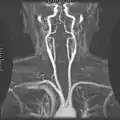

Магнитно-резонансная ангиография.- Внутренняя сонная артерия.

- Внутренняя сонная артерия.